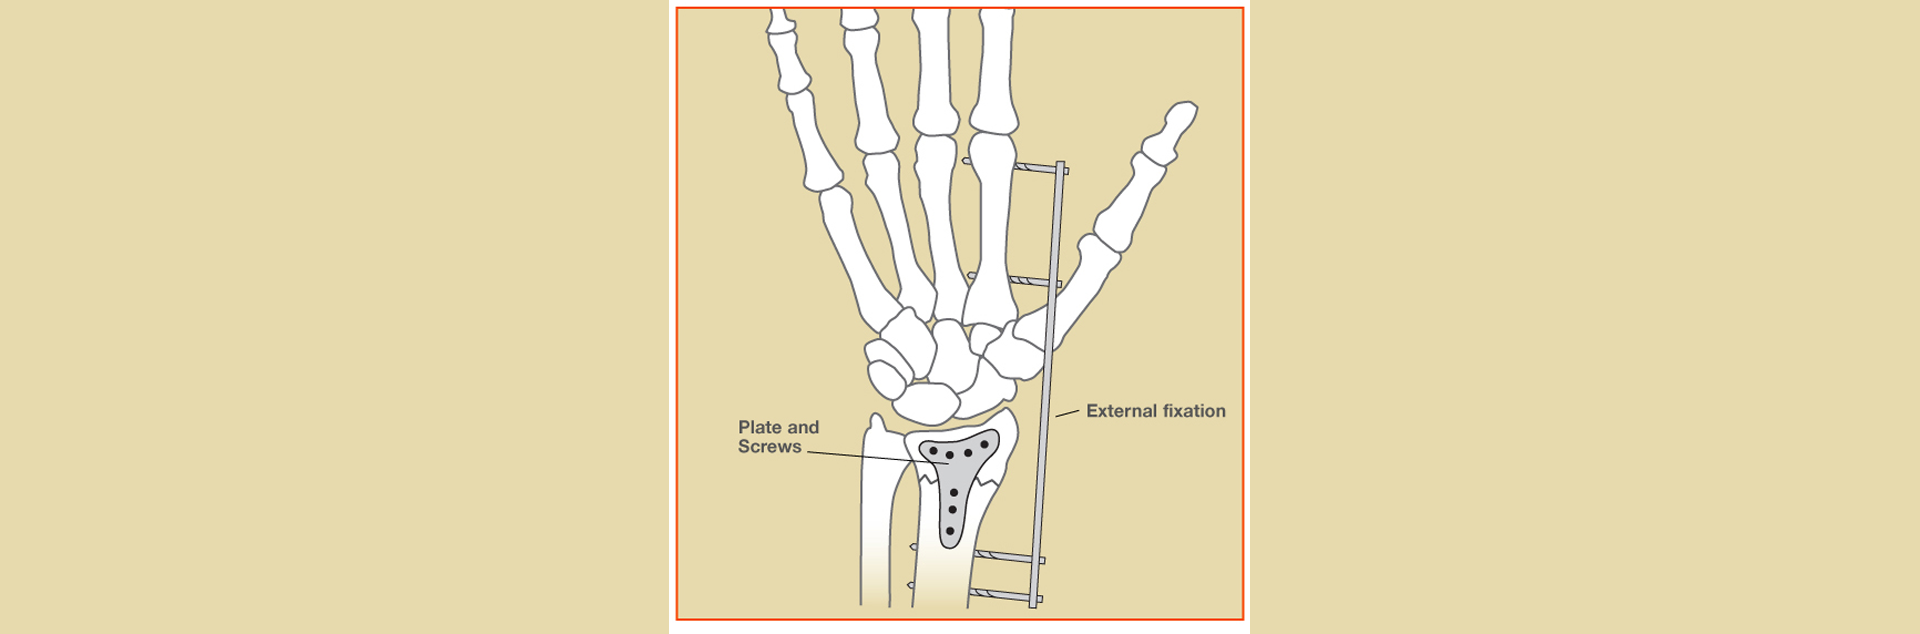

Surgical Techniques

Depending on the fracture type, our surgeons may perform:

- Open Reduction and Internal Fixation (ORIF): Using plates and screws to accurately realign the bone.

- External Fixation: A stabilizing frame outside the wrist for severe or open fractures.